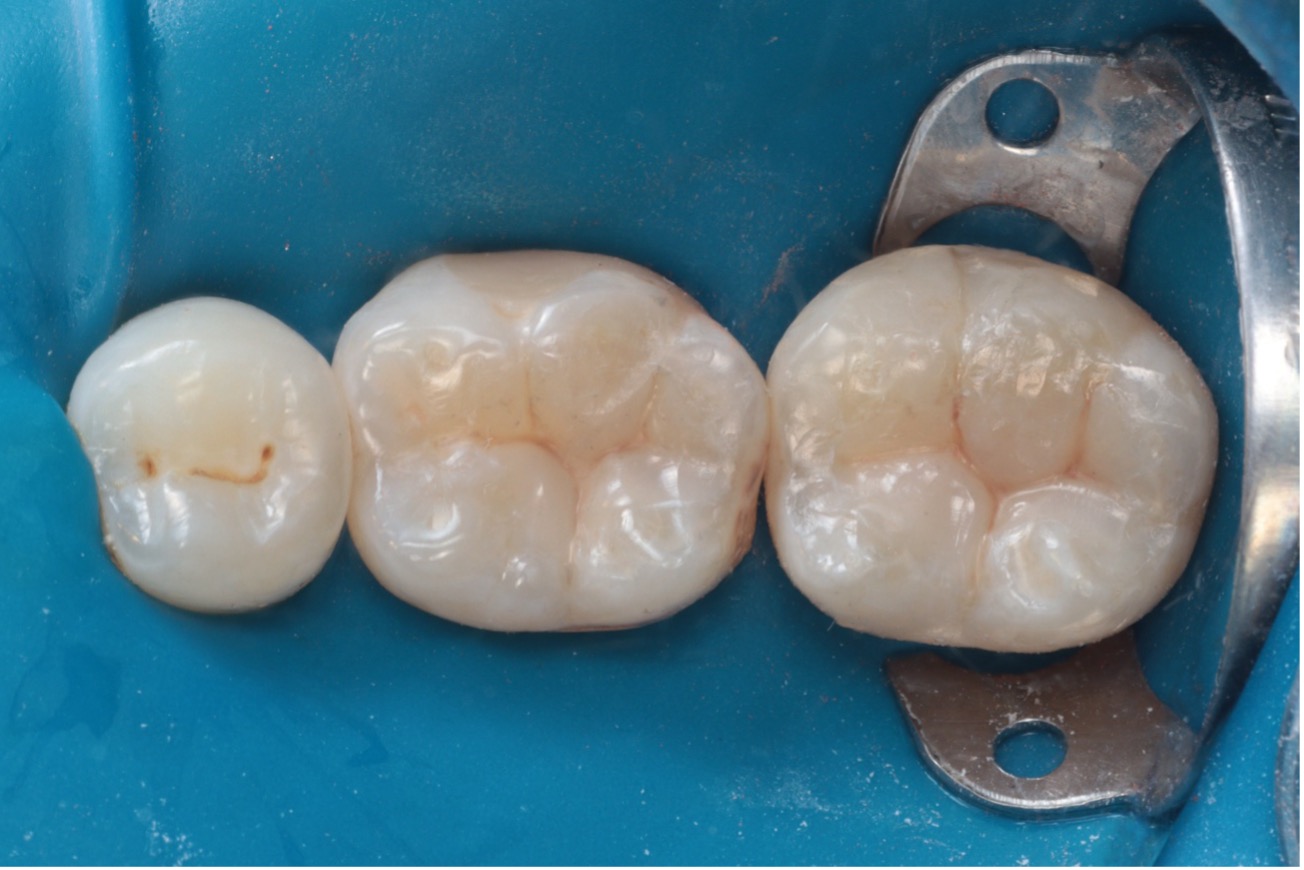

As restaurações em amálgama foram cuidadosamente removidas com brocas diamantadas em alta rotação, e a dentina comprometida foi eliminada com broca esférica carbide em baixa rotação. A cavidade foi então limpa com pedra-pomes e água para remoção de resíduos (Figura 3).

Figura 3 – Remoção do amálgama